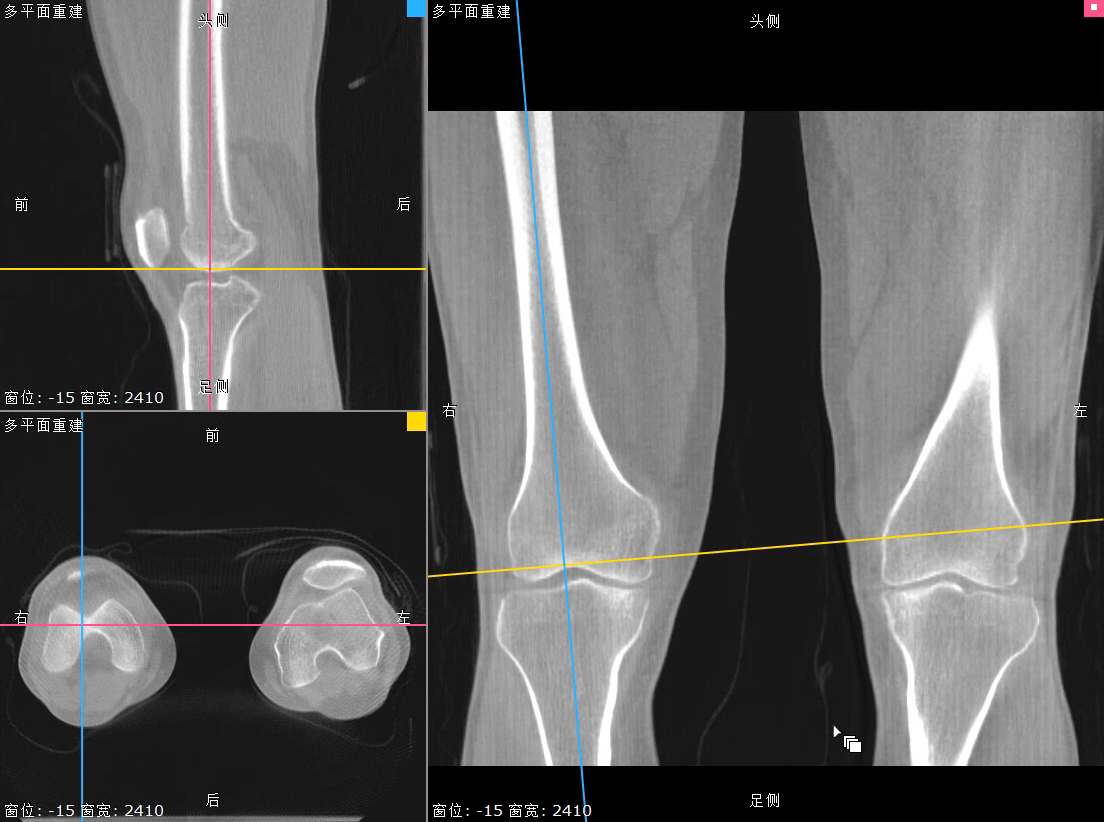

对于安健科技“WR-3D负重位动态三维影像重建系统”技术的问世,主要解决了两大核心问题:1、解决了普放DR漏诊率高的现状,常规DR设备仅有某一角度的二维影像、密度信息极差,而WR-3D能获得更丰富的诊断信息,多角度拍摄三维重建影像,任意角度任意切面以及高敏感的密度信息;2、解决了CT无法获得立位(负重位)的三维影像,WR-3D无论是在断层图像重建、MPR多平面重建、VR体绘制都有着优异的表现,而对于临床诊断尤其是骨科,负重位的影像更具有临床价值。患者在负重位状态下肌肉状态、关节间隙及骨骼力线等都与患者平躺时是明显不同的。因此WR-3D在术前精准规划与术后精准评估方面有其非常重要的临床价值。

(负重位状态下WR-3D MPR多平面重建)